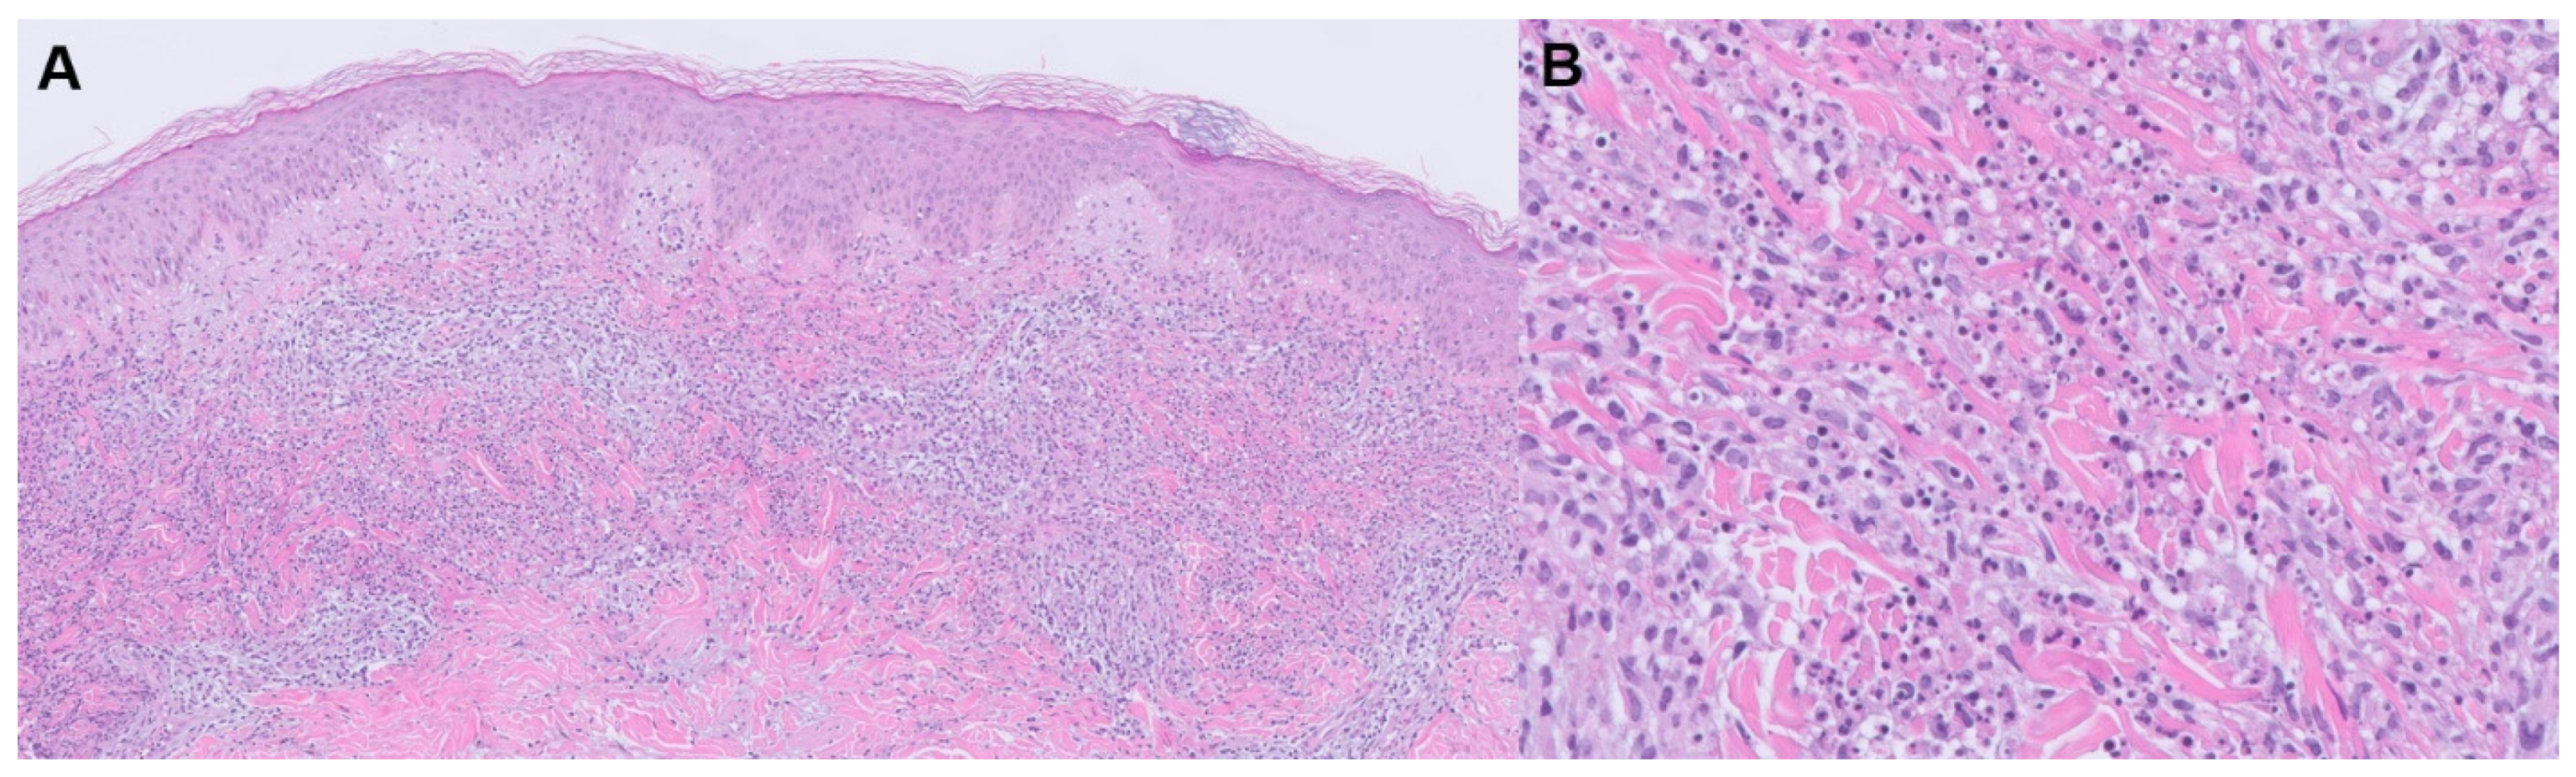

3.2.1. Sweet Syndrome

| Sweet Syndrome | Acute-onset tender plaques or nodules, fever, arthralgia, ophthalmologic manifestations, headaches, oral or genital lesions | -Diffuse, dense neutrophilic infiltrate in the reticular dermis with interstitial leukocytoclastic nuclear debris -Epidermis often spared, but spongiosis and subcorneal pustules may be present | -Clinically: infection -Histologically: bowel bypass syndrome, erythema elevatum diutinum, granuloma faciale, halogenoderma, leukemia cutis, leukocytoclastic vasculitis, lobular neutrophilic panniculitides, neutrophilic eccrine hidradenitis, pyoderma gangrenosum, rheumatoid neutrophilic dermatitis | -First-line: systemic or topical corticosteroids, potassium iodide, colchicine -Second-line: indomethacin, clofazimine, cyclosporine, dapsone -Reported success in refractory cases: rituximab, anti-TNF-α agents, IL1 receptor antagonists, and granulocyte and monocyte adsorption apheresis |